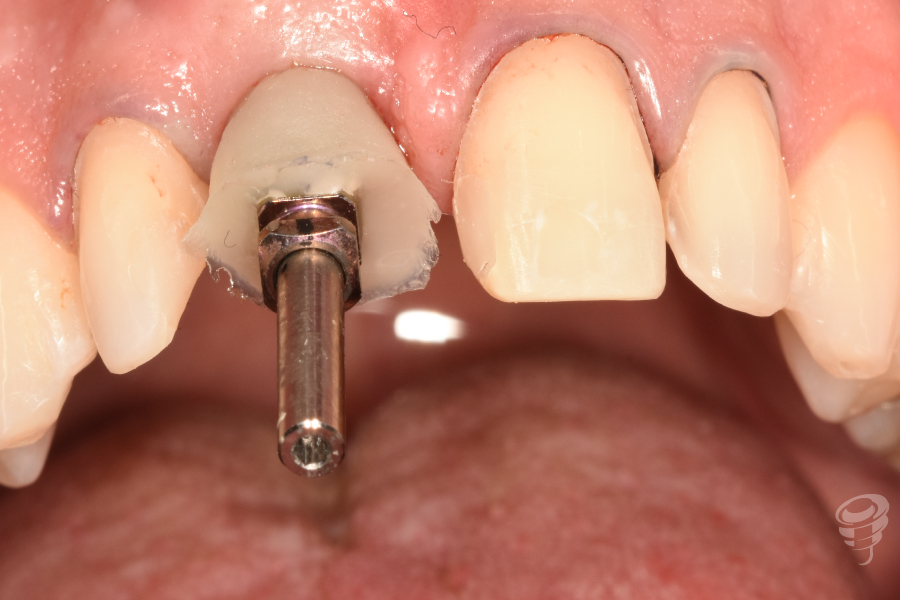

- Provisionalización: Pilar titanio personalizado + corona provisional de resina acrílica (sin contacto oclusal), con la colocación de puntos suspensores para estabilizar la encía y márgenes gingivales.

Figura 22

Figura 23

Figura 24

Figura 25